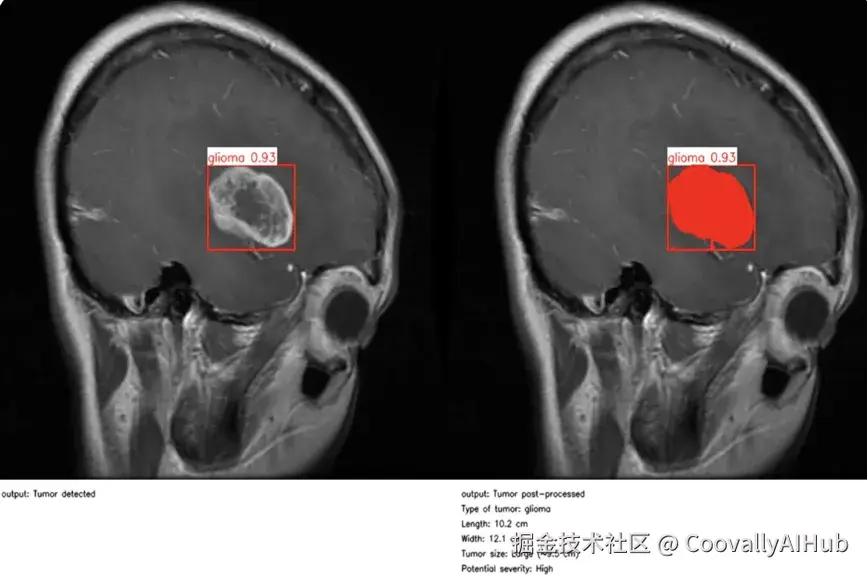

• 利用人工智能视觉技术实现个性化医疗服务

同样,随着计算机视觉成为日常临床工作流程的一部分,医疗保健领域也取得了重大进展。在医疗环境中,精确性和时间性至关重要,而计算机视觉研究和人工智能驱动的图像分析正在让临床医生做出更快、更明智的决定。

医疗保健的许多领域都是如此。以眼科为例。在英国莫菲尔德眼科医院,研究人员开发了RETFound,这是医学领域首批人工智能基础模型之一,也是眼科领域的首个人工智能基础模型。

通过自我监督学习,该模型在 160 万张视网膜图像上进行了训练,可以detect 糖尿病视网膜病变和青光眼等威胁视力的疾病,甚至可以根据细微的视网膜线索预测心力衰竭、中风和帕金森病等更广泛的全身性疾病。